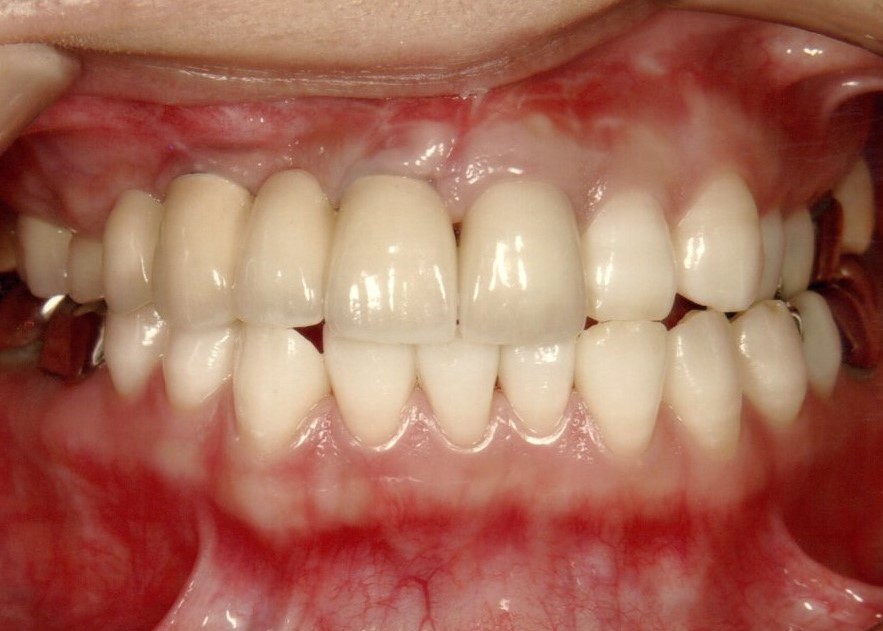

入れ歯装着前

入れ歯は一般的には歯を多く失った時に行う治療法で、型を取って、噛み合わせを記録して製作する取り外し可能な物です。保険で製作できますが、薄くて快適な入れ歯や、バネのないノンクラスプデンチャーは自費治療になります。

治療前

下の歯は歯周病でグラグラです。

お口の中の状態